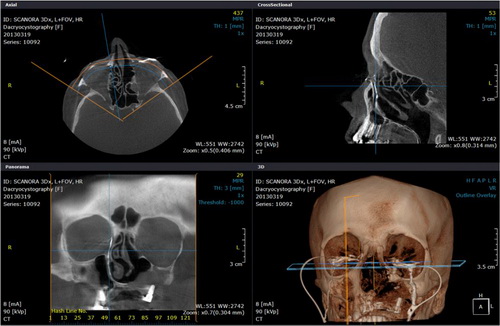

Fogászati CT (CBCT)

A panoráma-röntgen 2 dimenziós képalkotásához képest a fogászati CT 3 dimenziós képalkotása tizedmilliméter pontossággal ábrázolja az állkapcsokat, a bennük elhelyezkedő fogak helyzetét. Ezáltal olyan plusz információkhoz juthatunk (milyen vastag és milyen sűrűségű az állcsont csontszerkezete, környező anatómiai képletek), amelyek szájsebészeti beavatkozások sikeres elvégzéséhez nélkülözhetetlenek.

Ezen vizsgálómódszerrel állkapocs-ízületi problémáktól szenvedő betegek kaphatnak a gyógyulásukhoz szükséges pontos diagnózishoz, illetve krónikus arcüreg gyulladás forrása is kimutatható e korszerű technológiával.